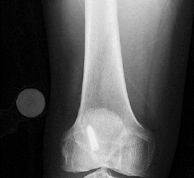

A 9-year-old boy sustains a distal femur fracture. Radiographs demonstrate a fracture line propagating along the physis and exiting through the metaphysis, producing a small metaphyseal bone fragment (Thurston-Holland fragment). Based on the Salter-Harris classification, what type of fracture is this, and what is the typical expectation regarding growth arrest?

Correct Answer: Type II; Most common type, usually does not affect growth, though distal femur location carries a uniquely higher risk

Explanation:

A fracture that propagates through the physis and exits through the metaphysis (creating a Thurston-Holland fragment) is a Salter-Harris Type II fracture. It is the most common physeal fracture pattern. Because the germinal layers of the physis remain attached to the epiphysis, the general prognosis for growth is good. However, one must recognize that Type II fractures of the distal femur inherently carry a high risk of growth arrest (up to 40-50%) compared to other locations.